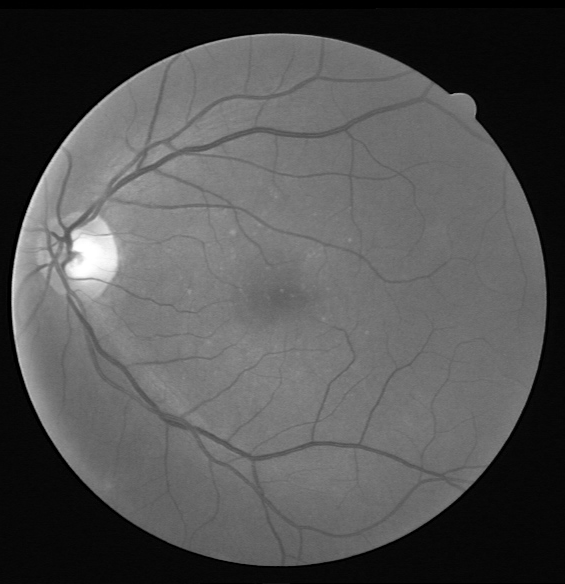

Refer to caption

(a) Original image

(b) Ground truth

(c) Binary mask

(d) Original image

(e) Ground truth

(f) Binary mask

Figure 7: Visual results for two sample DRIVE images.

Results for DRIVE Test Images: Quantitative results of BLCB-CNN for all DRIVE images are computed, which shows that the proposed method achieves an average accuracy of 96.22. The average sensitivity/specificity value of 81.57/97.65 also indicates the model’s ability to accurately segment vessel pixels (including thin vessels). The AUC results are also consistent with the accuracy obtained for all the images. Figure 7 demonstrates the visual outcomes for two sample DRIVE images. It can be observed that the proposed method segmented both thin and thick vessels much closer to ground truth binary masks. This is further evident from the focused rectangular areas of the output/ground-truth images.